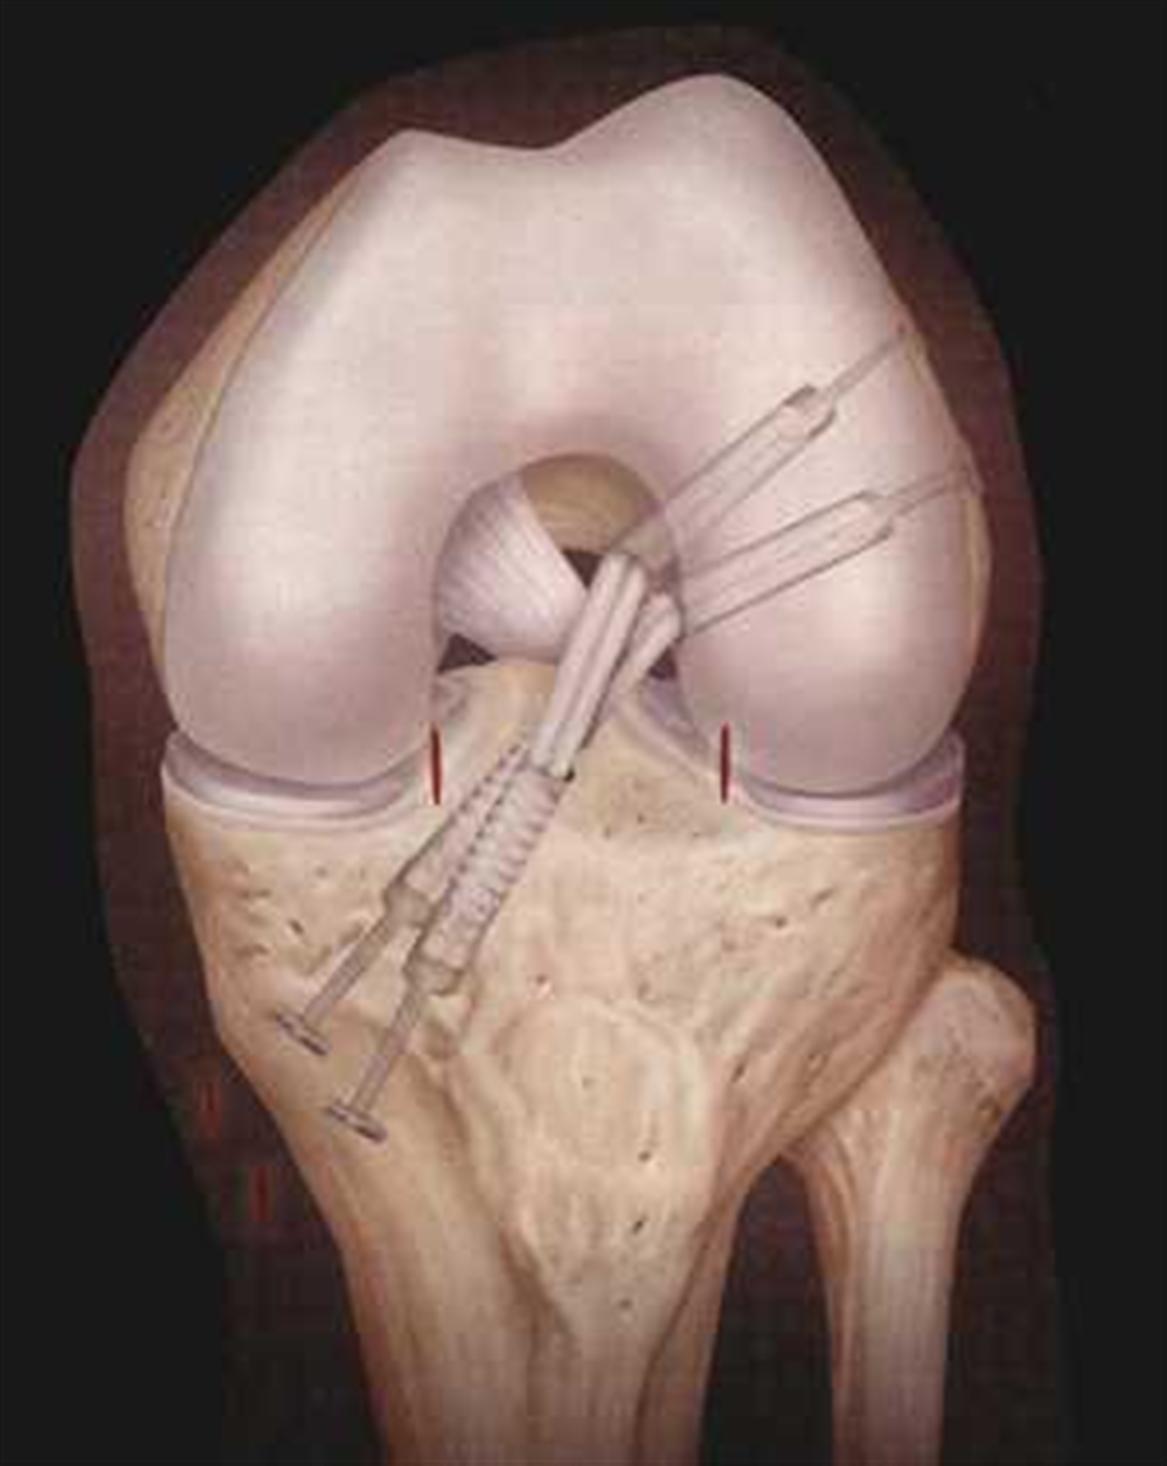

Schemadarstellungen der Kreuzbandoperation

Der Eingriff kann heute arthroskopisch assistiert im Rahmen einer Kniegelenksspiegelung (arthroskopische Kreuzbandoperation) durchgeführt werden: Dabei werden neben drei Einstichen zur Arthroskopie ein ca. 3 cm großer Schnitt am Schienbeinkopf vorgenommen. Zur Kreuzbandersatzplastik werden entweder die beiden Pes anserinus-Sehnen (Gracilis und Semitendinosus) oder das mittlere Drittel der Patellarsehne verwendet. Vom Hautschnitt am Schienbeinkopf werden die Sehnen mit einem Sehnenstripper entnommen. Man gewinnt mit der Semitendinosus- und Gracilissehne zwei Sehnen von einer Länge von ca. 22 bis 28 cm. Die beiden Sehnen werden unter einer Vorspannung miteinander vernäht und als Ersatz für das gerissene Kreuzband welches nicht genäht werden kann und vorher entfernt wird in das Kniegelenk eingezogen: Nach der Entnahme der Sehnen werden arthroskopisch die Stümpfe des rupturierten Kreuzbandes entfernt und mit Hilfe eines tibialen Zielgerätes ein Draht in den Schienbeinkopf eingebracht, der zentral im Stumpf des gerissenen Kreuzbandes tibial in das Gelenk eintritt. Der Draht wird anschließend mit einem Hohlbohrer überbohrt. Der Durchmesser des Bohrkanals richtet sich nach dem Durchmesser des angefertigten Sehnentransplantates, zwischen 7 und 10 mm liegend. Durch den tibialen Bohrkanal wird ein Zielgerät für den Femur eingebracht. Mit Hilfe des femoralen Zielgerätes wird jetzt der femorale Bohrkanal hergestellt. Meist ist auch hier die korrekte Position des femoralen Kreuzbandansatzes durch einen noch erhaltenen kleinen Bandstumpf gegeben. Mit Hilfe des Zielgerätes wird jetzt ein weiterer Draht in den Femur eingebracht. Dieser wird überbohrt. In den tibialen und femoralen Bohrkanal wird jetzt das Sehnentransplantat eingezogen. Im Oberschenkelknochen wird das Transplantat mit einem kleinen Titanplättchen (Endoloop) oder mit einer seitlich eingebrachten Hohlschraube fixiert (Transfix-Schraube). Das aus dem tibialen Kanal herausreichende Ende des Transplantates wird nun kräftig angespannt und mit einer resorbierbaren Interferenzschraube durch Verklemmung befestigt und auch mit einer weiteren Schraube im Schienbein fixiert.

Zunehmend wird heute auch die Rekonstruktion des vorderen Kreuzbandes in Doppelbündeltechnik empfohlen. Diese ist der Anatomie des Vorderen Kreuzbandes noch näher und dadurch auch "physiologischer", technisch jedoch komplex und aufwendiger durchzuführen. Die Vor- und Nachteile der neuen Technik sind noch nicht abschliessend geklärt.